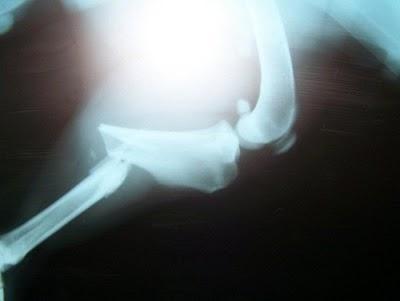

Como consecuencia del atropello tiene la pata trasera fracturada.

Necesitamos donativos para poder operarla.

El presupuesto es de 700 euros, una vez se recoja y se opere scanearemos factura a quien nos la pida.